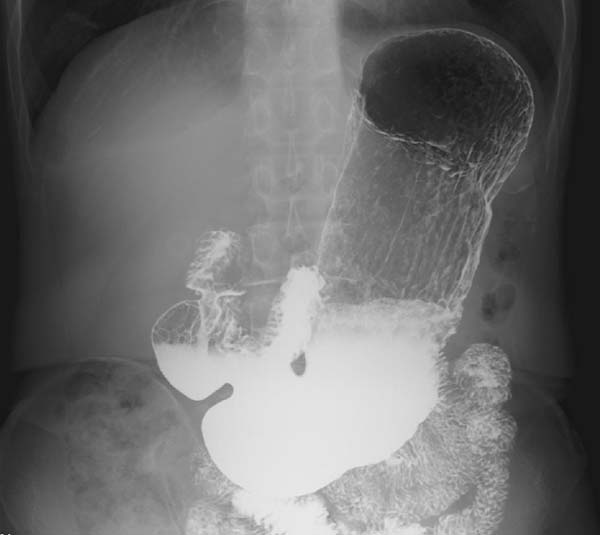

患者入院后,韩加刚团队启动多学科评估,联合消化内科、麻醉手术中心、营养科开展全面检查与病情研判。通过上消化道造影、腹部超声、胃动力检测等精准检查,明确患者为重度胃下垂(胃下垂至盆腔),伴随胃排空延迟、消化吸收功能障碍。经过讨论确定实施腹腔镜微创远端胃大部切除+悬吊固定术。该术式仅在腹部做3个0.5至1厘米的小孔,借助高清腹腔镜系统清晰显露腹腔结构,具有创伤小、出血少、疼痛轻、恢复快、并发症少等优势。

上消化道造影显示重度胃下垂